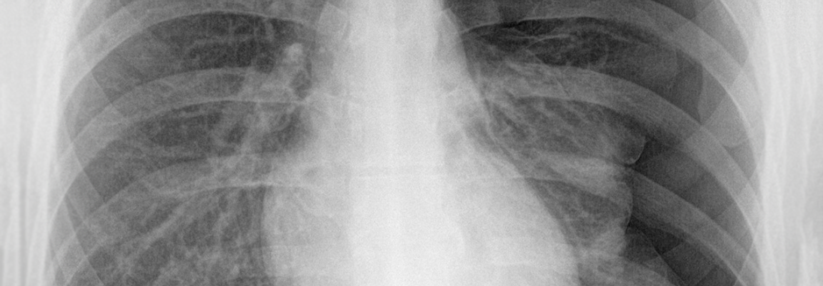

© wikipedia.org/Hellerhoff, CC BY-SA 3.0

Am besten lässt sich ein Pneumothorax im Röntgenthorax (in Expiration und Inspiration) oder im CT darstellen.

Nach Eingriffen wie Pleurapunktion oder Legen eines Subklavia-Katheters sollte immer eine Röntgen-Throaxaufnahme erfolgen, um einen iatrogenen Pneumothorax auszuschließen.